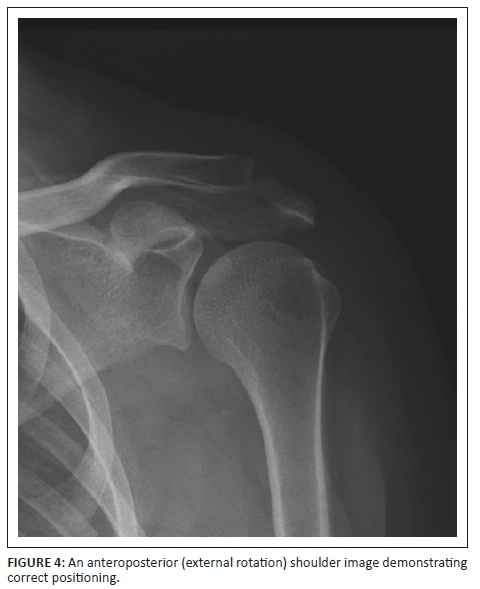

Various factors were listed in a specific question, and the participants had to indicate which of these factors were important to ensure that the AP external rotation shoulder projection was demonstrated optimally. Most of the students (93%) and radiographers (71%) selected the correct answer, namely that all the indicated factors were required to ensure optimal positioning of this projection (Figure 3). This difference observed between students and radiographers was statistically significant (p = 0.0099). However, 29% of radiographers only indicated that the hand should have been in supination, and 7% of students indicated that only the humeral epicondyles should be parallel to the imaging receptor (IR). Figure 4 demonstrates an AP (external rotation) shoulder image that adheres to the positioning criteria.

Participants had to indicate the positioning factors that are of importance to ensure that an AP projection (external rotation) of the shoulder is optimal for diagnosis. These factors include some of the criteria applicable during imaging of the AP projection (external rotation) of the shoulder. It was noteworthy that most of the students indicated that all the factors, namely the hand in supination, arm abduction and the humeral epicondyles being parallel to the cassette, are of importance to obtain an optimal AP projection (external rotation) of the shoulder. A significant difference between the students and the radiographers were observed. It is clear that 29% of the radiographers did not know the positioning factors for the AP projection (external rotation), which could cause that these factors will be ignored during positioning, and consequently, the AP (external rotation) images would not adhere to the criteria outlined by the literature for an AP image of the shoulder. It is possible that the student radiographers answered this question correctly because they have obtained the theoretical training recently compared to the radiographers who completed their certificate or diploma or degree many years ago.